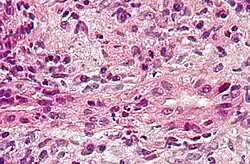

Description de cette image, également commentée ci-après

Coupe histologique d'une cholangite biliaire primitive montrant l'inflammation et la lésion des voies biliaires. Coloration à l'hématoxyline et à l'éosine.